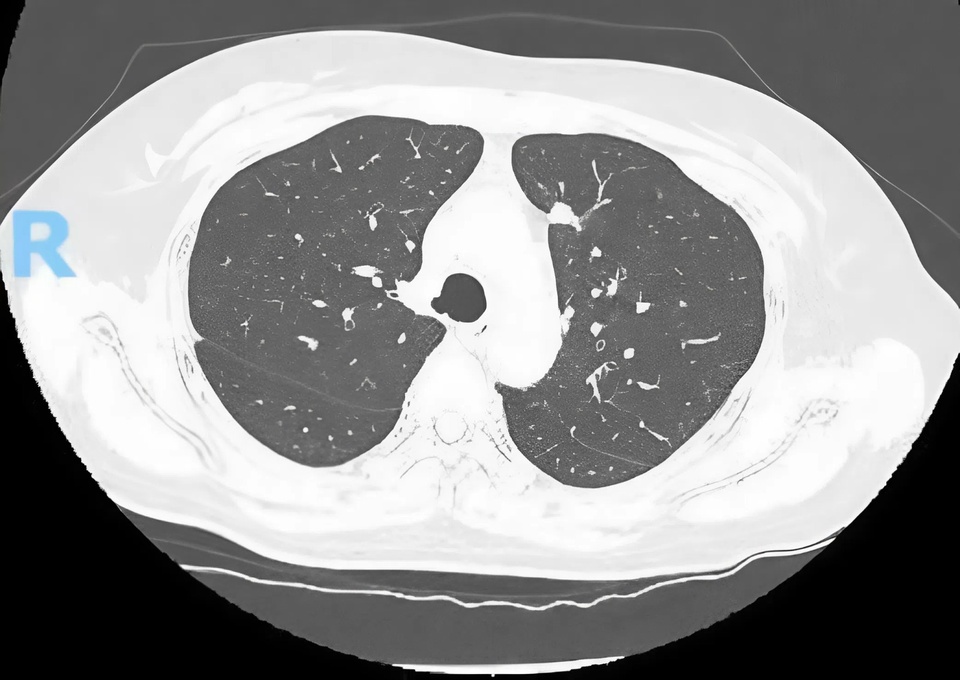

Từ những nốt mờ nhỏ tình cờ phát hiện khi tầm soát sức khỏe, hai bệnh nhân ở TP.HCM được chẩn đoán ung thư. Ảnh: BVCC.

Bệnh nhân N.T.K.C. (50 tuổi, TP.HCM) được phát hiện nốt mờ 11 mm ở thùy trên phổi phải khi chụp CT ngực liều thấp trong đợt khám định kỳ. Dù không có triệu chứng bất thường, kết quả PET/CT cho thấy dấu hiệu nghi ngờ ung thư phổi giai đoạn sớm.

Tương tự, bệnh nhân L.T.H. (55 tuổi, TP.HCM) cũng phát hiện nốt mờ 9 mm ở phổi phải khi chụp CT ngực độ phân giải cao. Kết quả hội chẩn xác định ung thư phổi giai đoạn sớm (T1aN0M0).

TS.BS Nguyễn Hoàng Bình khuyến cáo, nốt mờ nhỏ ở phổi thường không có triệu chứng, chỉ phát hiện tình cờ khi tầm soát. Do đó, chụp CT ngực liều thấp (Low-Dose CT Scan) là công cụ hữu hiệu, được Hiệp hội Lồng ngực Hoa Kỳ (ATS) và Hiệp hội Ung thư Việt Nam khuyến nghị cho nhóm nguy cơ cao: người trên 50 tuổi, có tiền sử hút thuốc, làm việc trong môi trường ô nhiễm hoặc có người thân mắc ung thư phổi.